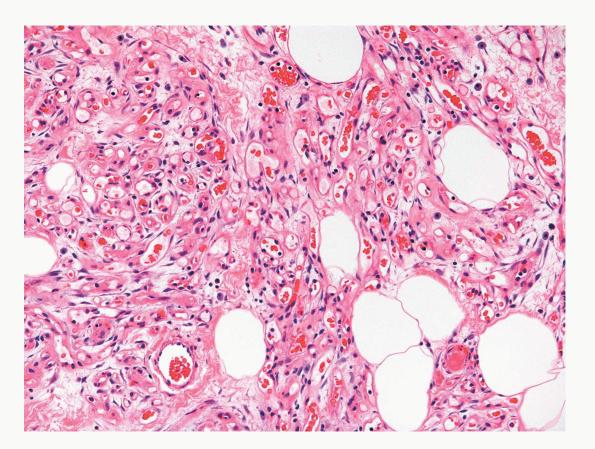

Angiolipoma = الشحموم الوعائي